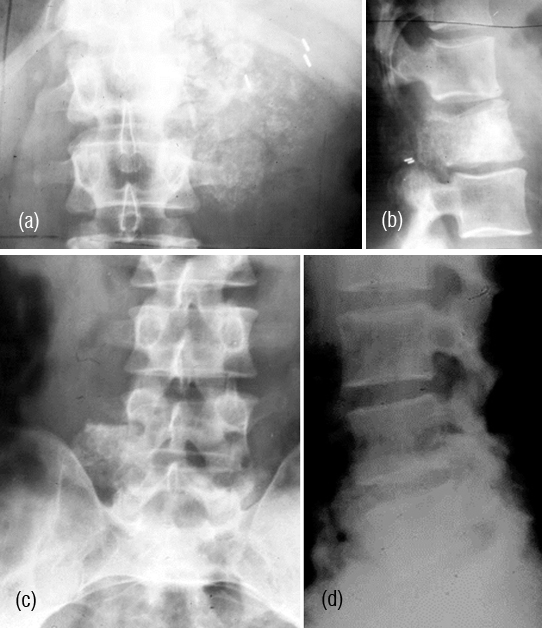

This is also a rare tumor and may involve the vertebral column. Radiological findings include lytic lesion with sclerosis and cartilaginous calcifications (Figure 9abcd). CT helps in identification of early calcifications. CT allows optimal detection and characterization of matrix mineralization, endosteal scalloping. MR imaging depicts the extent of marrow involvement and demonstration of soft tissue extension with mass formation. MRI shows the cartilaginous nature of the lesion by bright signals in T2 (Figure 10abcd).

Figure 9a,b: Chondrosarcoma of L1. Note the paravertebral ring like calcifications.

Figure 9: Chondrosarcoma of L5- (c) AP view, (d) Lateral view.

Figure 10: Chondrosarcoma L5 – (a) plain films, (b) CT helps in identification of small calcifications. (c) plain, (d) MRI.